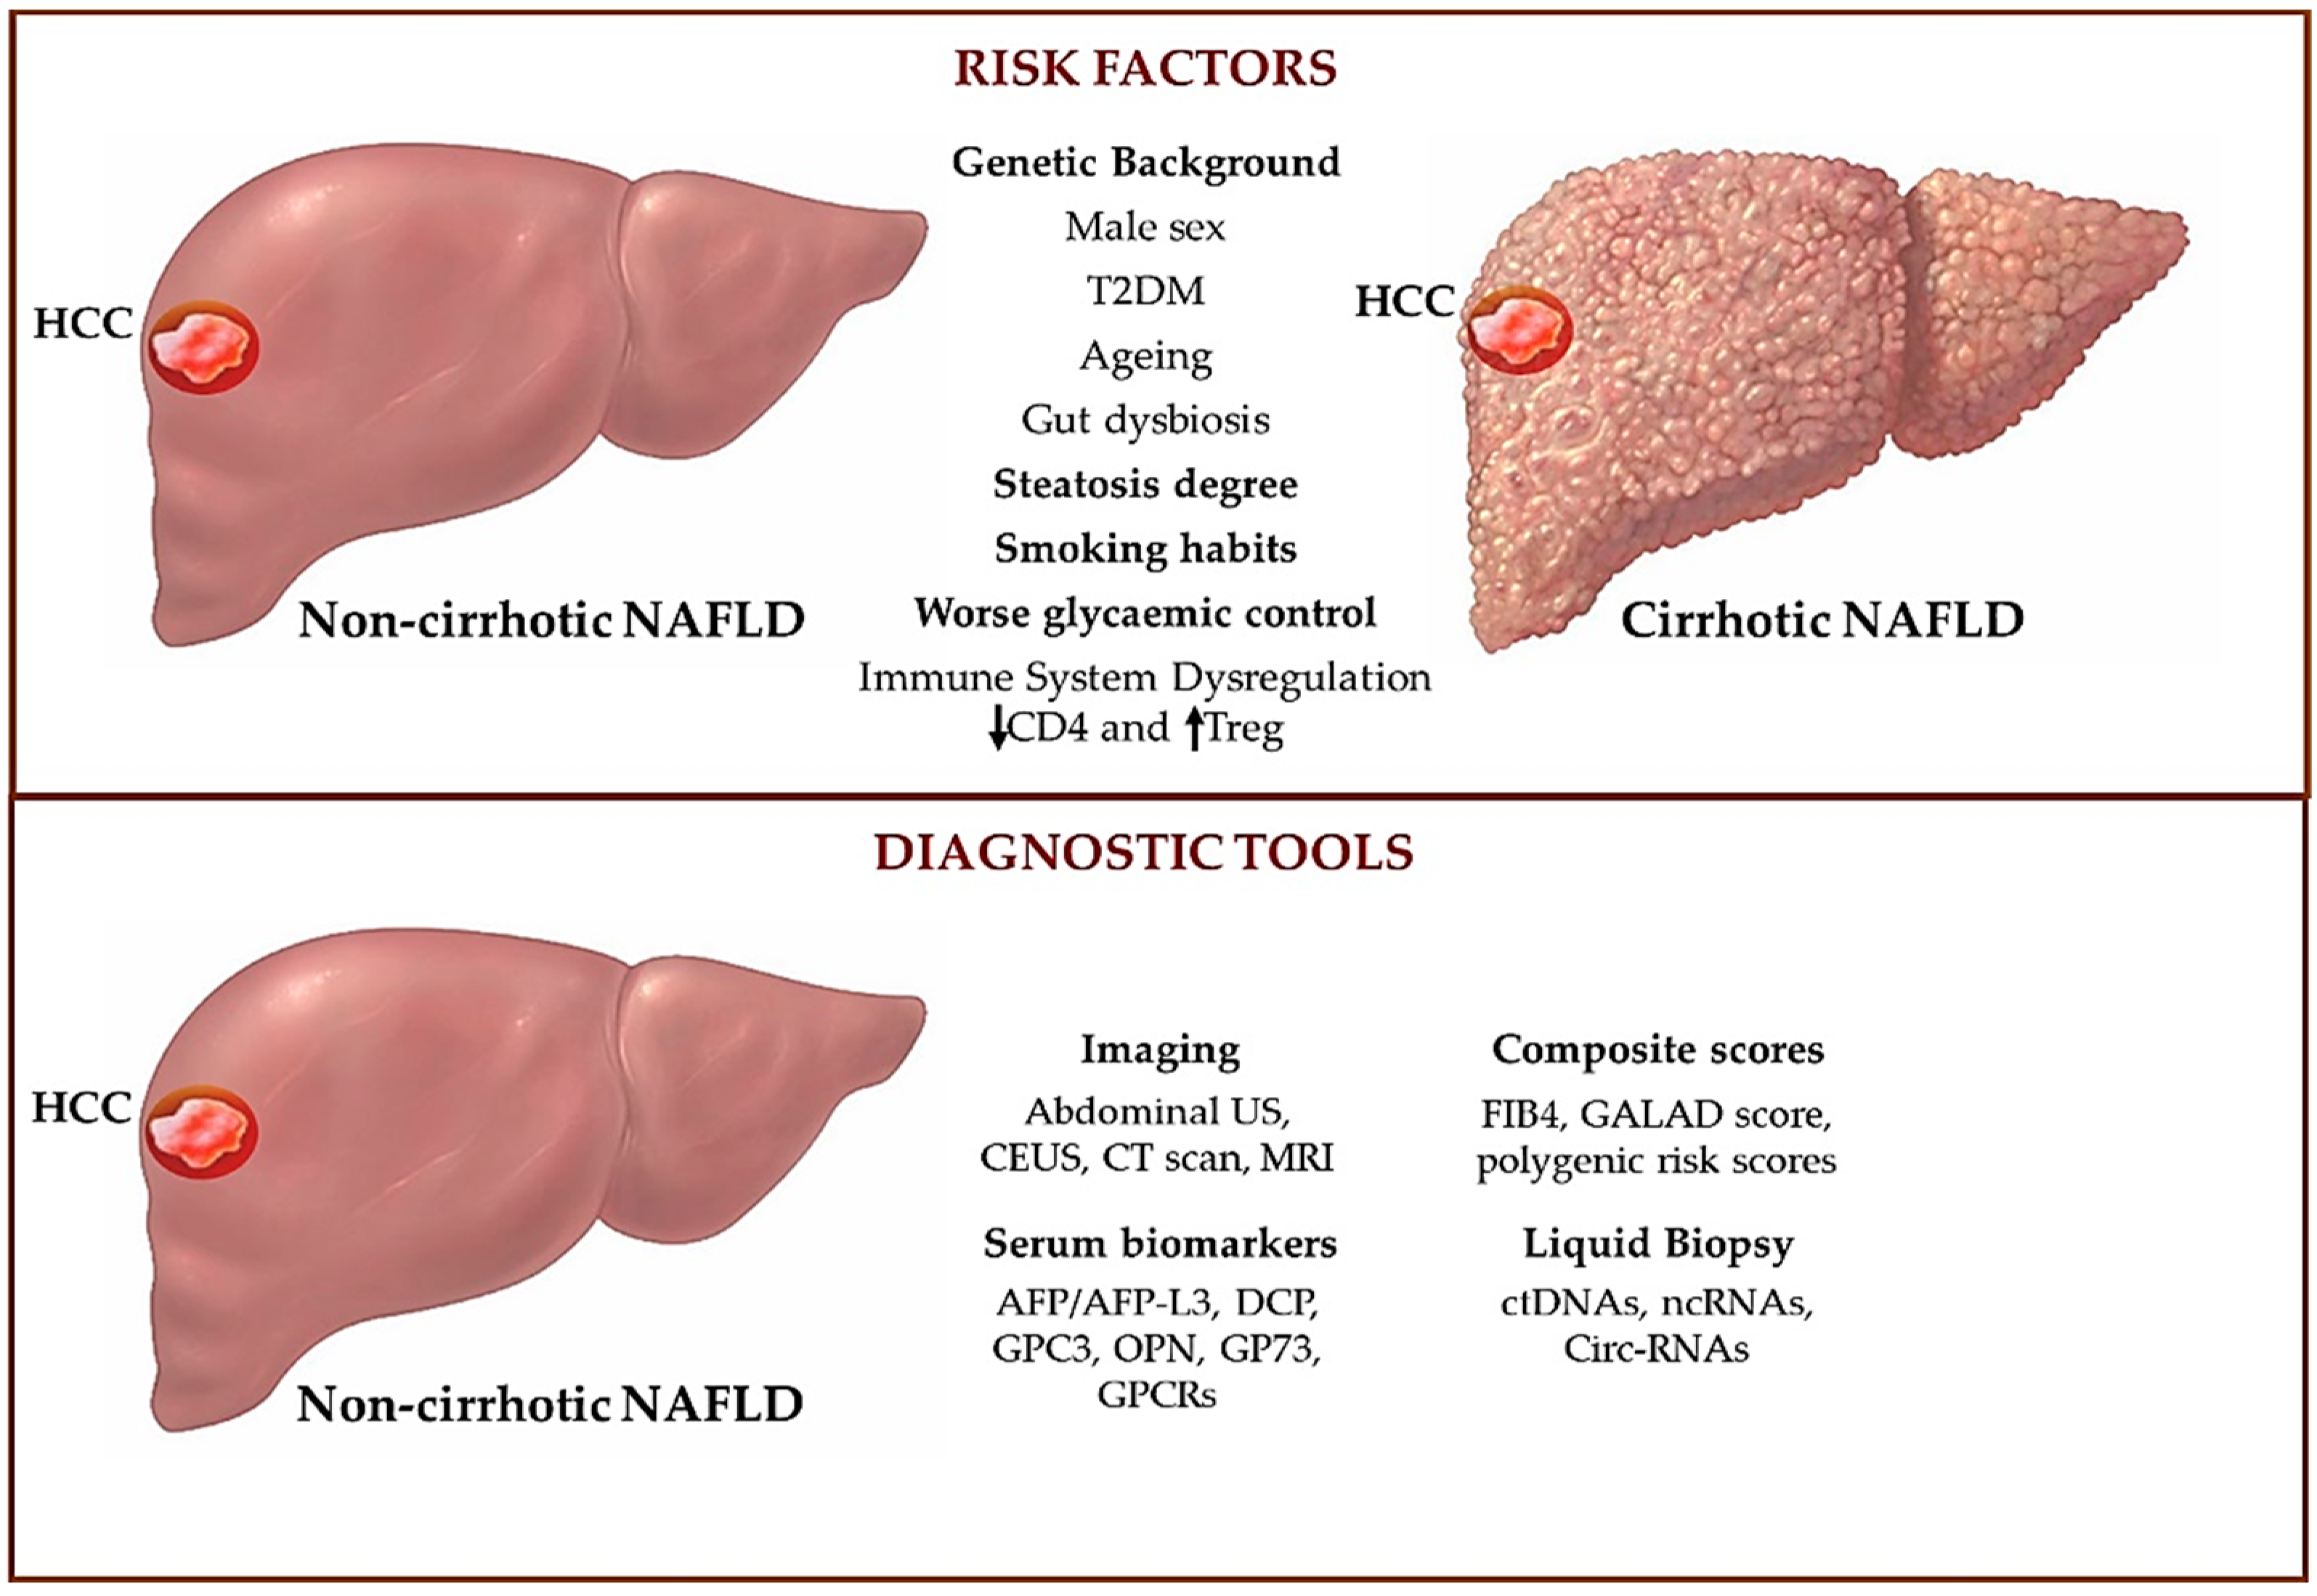

Biomedicines Free Full Text An Overview Of Hepatocellular Carcinoma